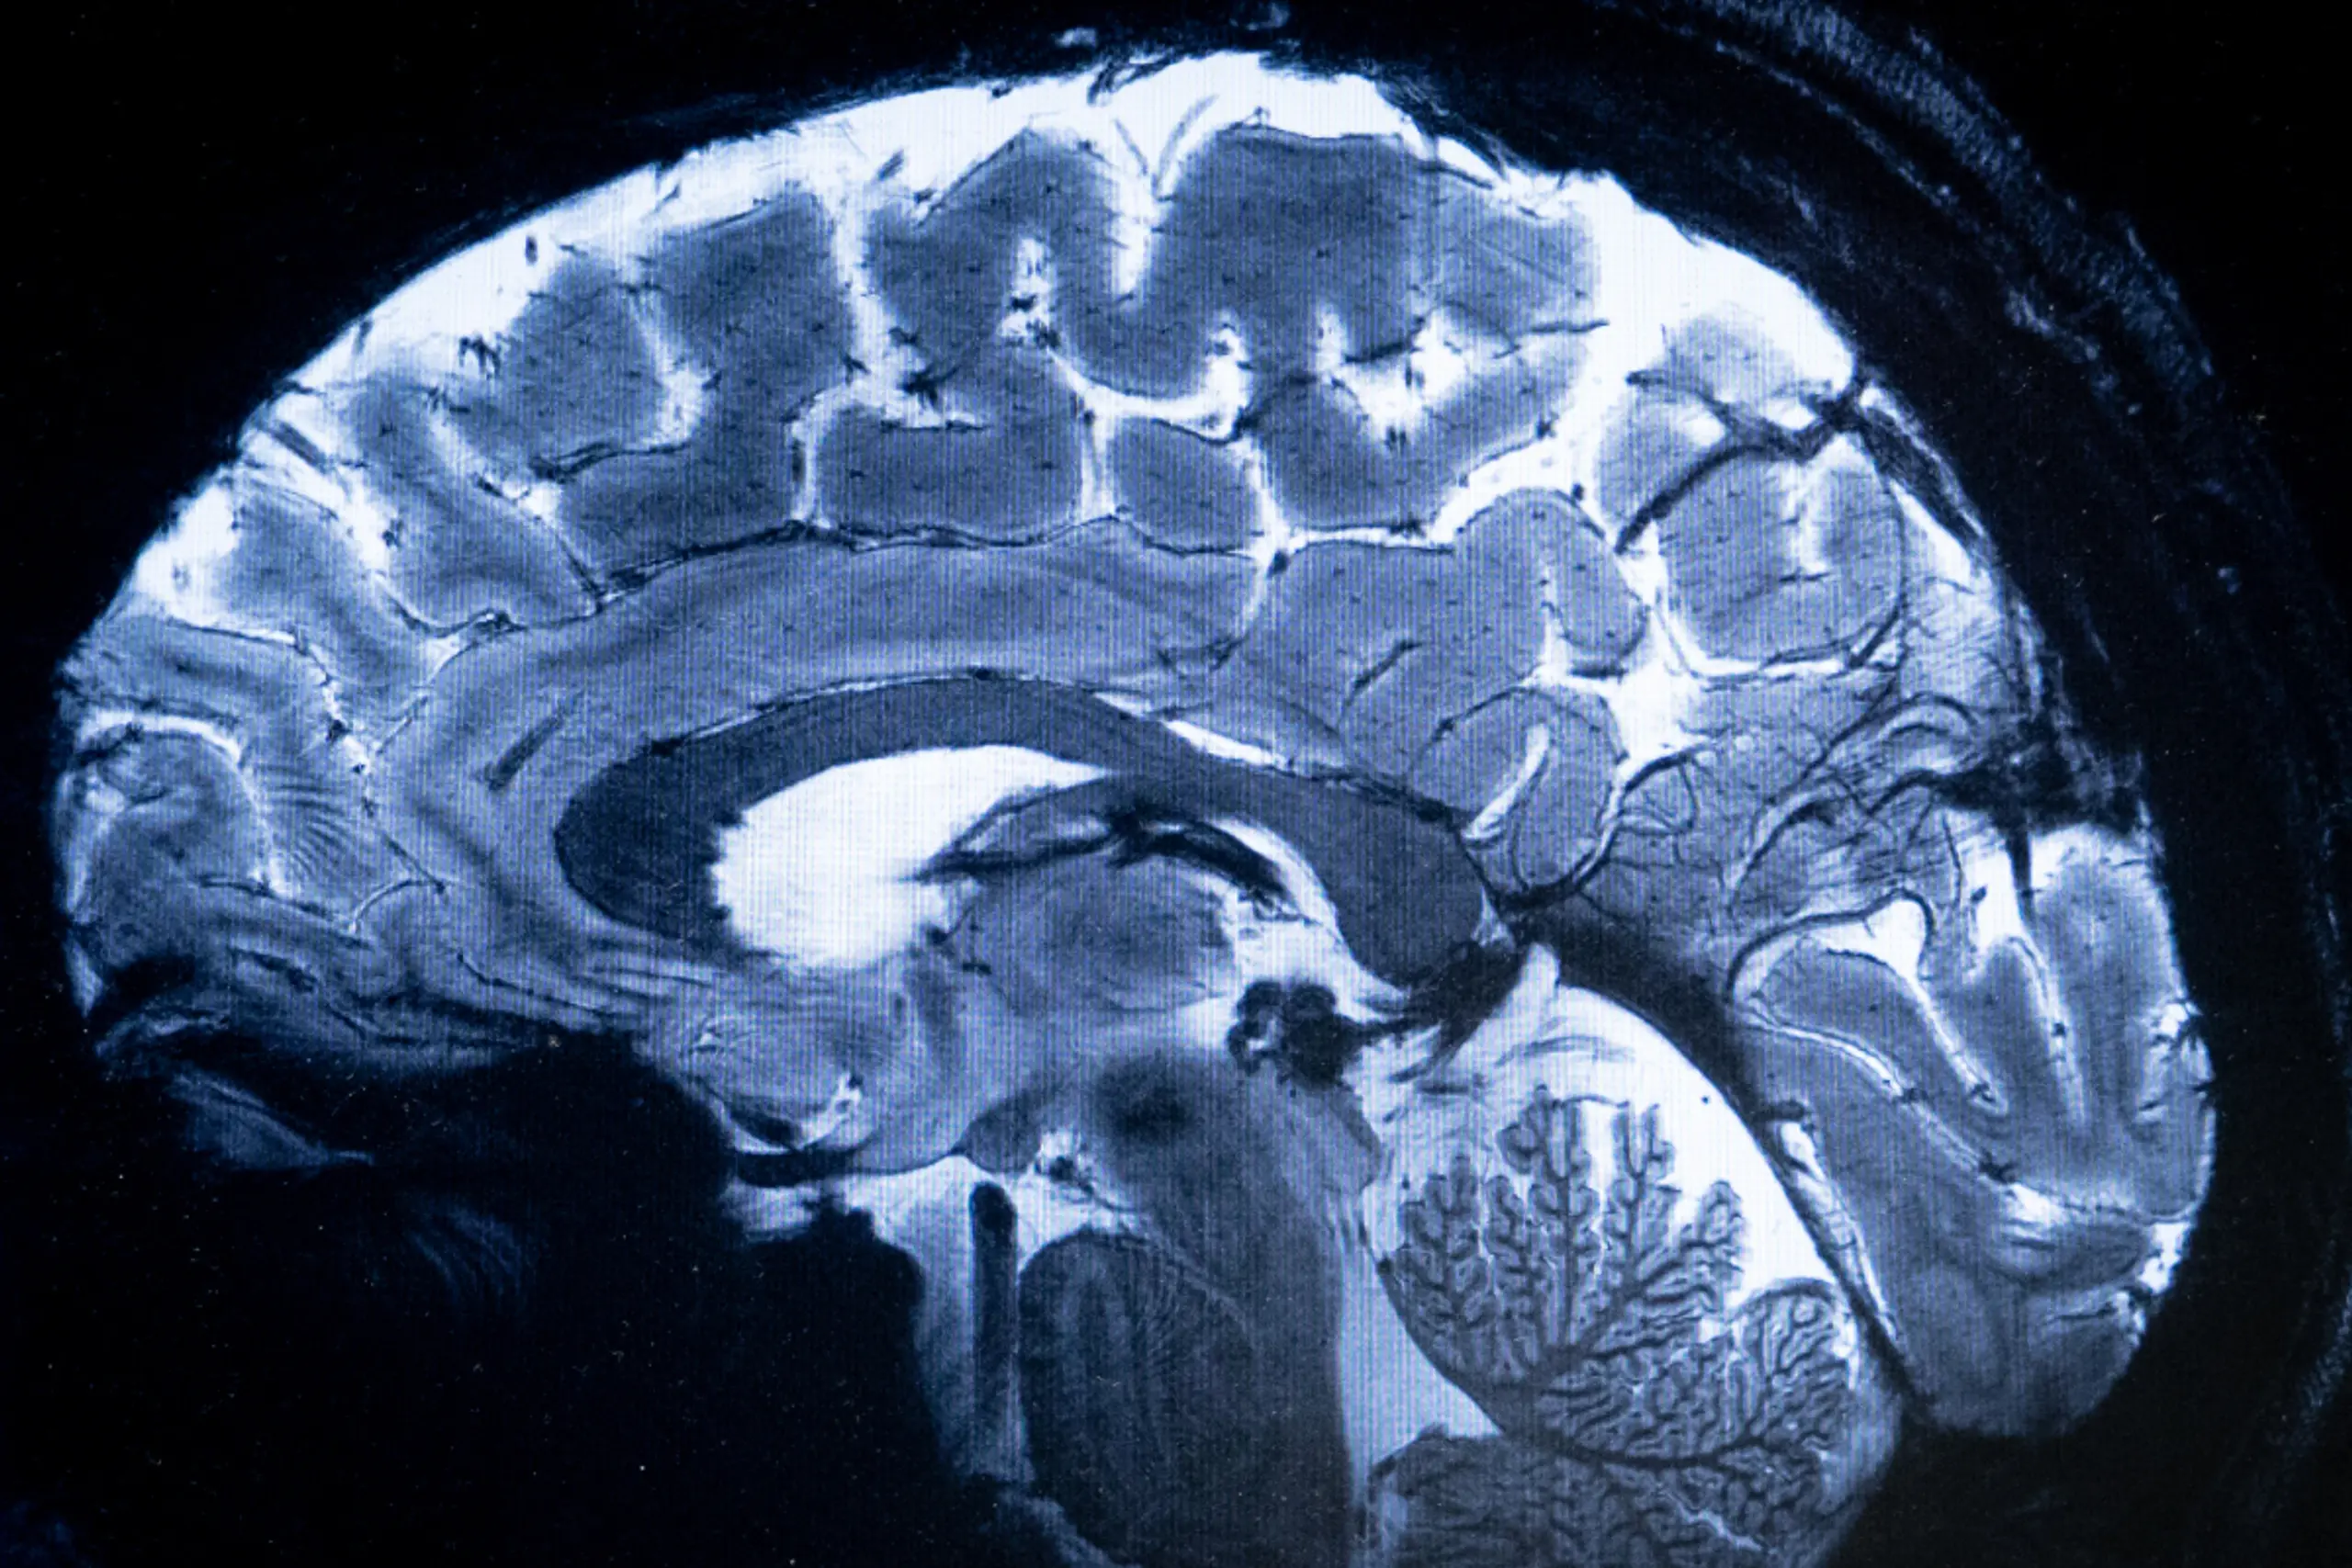

Bisher ging man davon aus, dass jedes Neuron an der richtigen Stelle sein müsse, damit das Gehirn richtig funktioniert. Die neue Forschung zeigt jedoch, dass falsch positionierte Neuronen nicht nur überleben, sondern auch die Funktion des normalen Großhirnrindenbereichs vollständig ersetzen können. Um zu diesem Ergebnis zu gelangen, untersuchten die Genfer Wissenschafter Mäuse mit Heterotopien. Damit sind Fehlbildungen gemeint, die durch fehlgeleitete Neuronen gekennzeichnet sind, die unter der Großhirnrinde an der falschen Stelle eine Masse bilden können. Dieses Phänomen tritt auch beim Menschen auf und kann zu epileptischen Anfällen und geistigen Defiziten führen.

Bei der Beobachtung dieser Nagetiere machte das Team der Unige eine überraschende Entdeckung: Diese falsch platzierten Neuronen bilden Schaltkreise, die fast identisch mit denen des normalen Kortex sind, mit ähnlichen Verbindungen zum Rest des Gehirns und zum Rückenmark. Und als die Wissenschafter den normalen Kortex dieser Mäuse während einer schwierigen sensorischen Aufgabe deaktivierten, funktionierten sie weiterhin normal.

Die falsch platzierten Neuronen hatten also die Aufgabe übernommen. Umgekehrt stellten die Wissenschafter fest, dass die Aufgabe vollständig fehlschlug, wenn sie diese abnormal platzierten Neuronen hemmten, was zeigt, dass diese falsch positionierten Neuronen für die sensorische Verarbeitung unerlässlich geworden waren.

"Es ist, als würde man ein ganzes Stadtviertel an einen anderen Ort verlegen und die Bewohnerinnen und Bewohner würden die gleichen Beziehungen, die gleichen Verbindungen zum Rest der Stadt aufrechterhalten", erklärte Sergi Roig-Puiggros, Postdoktorand am Departement für Grundlagenneurowissenschaften der Medizinischen Fakultät der Unige und Erstautor der Studie, in der Mitteilung.

Die Studie beleuchtet die evolutionären Mechanismen, durch die neue Gehirnstrukturen entstehen können. Sie eröffnet auch Perspektiven für die regenerative Medizin.